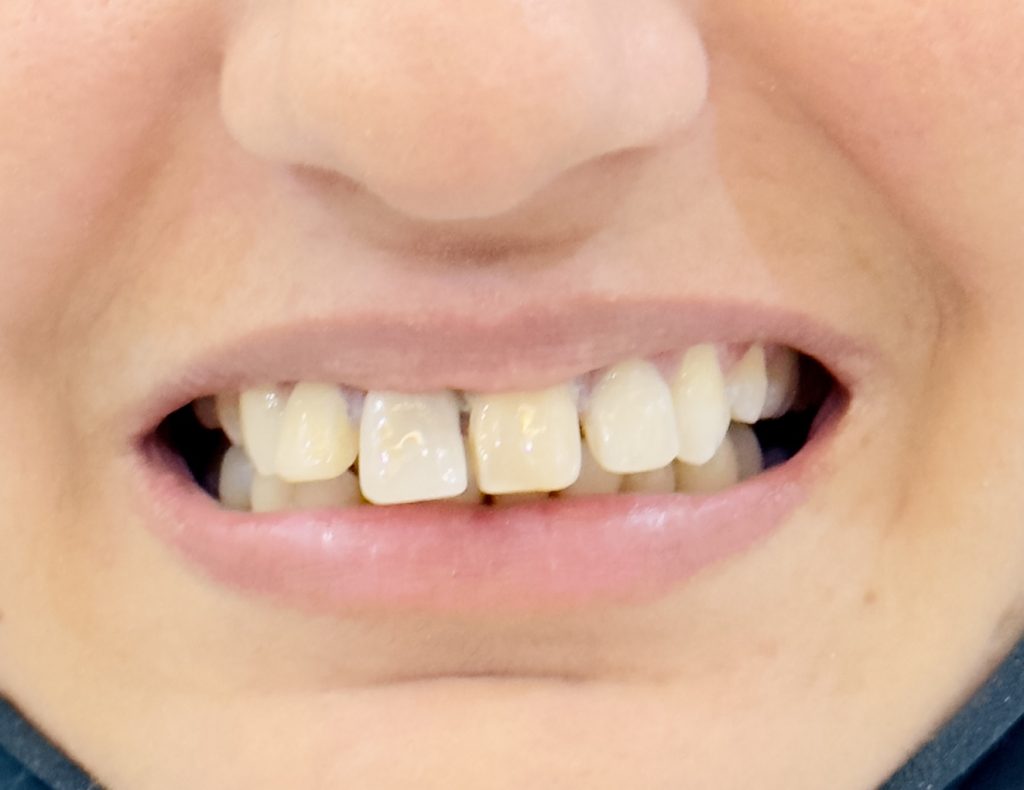

Chief Complaint

“I don’t like my smile. My front teeth are discolored and uneven. I want a natural and beautiful smile, but I cannot go for braces.”

- Moderate discoloration of tooth #11 and #21.

- Slight midline discrepancy; patient declined orthodontic correction.

- Post-traumatic discoloration due to pulpal necrosis.

- Residual esthetic defect after apexification.

- Asymmetrical incisal edges, smile cant, and uneven gingival margins.